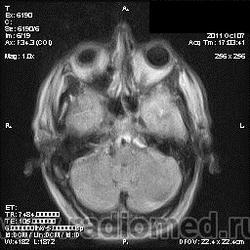

на МРТ - Определяется скопление крови в препонтинной цистерне, в проекции супраселлярной цистерны, в кортикальных бороздах полушарий головного мозга,  в проекции краниоспинального перехода. Выявляется горизонтальный уровень крови в задних рогах боковых желудочков. Боковые, третий желудочки резко расширены. Определяется перивентрикулярное повышение интенсивности сигнала от белого вещества головного мозга. Срединные структуры не смещены. Кортикальные борозды умеренно сглажены. Сильвиев водопровод прослеживается на всем протяжении. Отмечается смещение дна третьего желудочка каудально, с резким уменьшением размеров супраселлярной цистерны; базальные цистерны уменьшены в размере.

В проекции базальной артерии определяется аневризма размером до 4х6 мм.